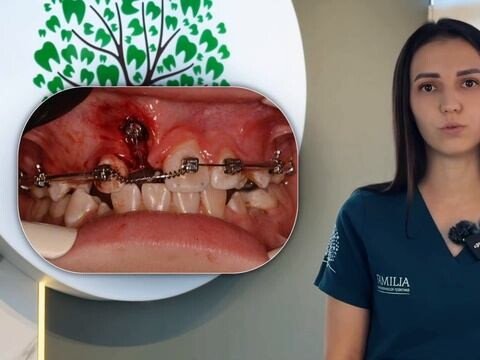

Видео

Юхнова Екатерина Александровна является стоматологом, а также работает в сфере пародонтологии. Самые распространенные причины для обращения к пародонтологу - повышенная чувствительность зубов и кровоточивость десен. Однако даже если мягкие ткани, окружающие ваши зубы, не беспокоят вас, все же важно периодически приезжать к врачу на осмотр, ведь на ранней стадии многие заболевания протекают без симптомов.

Христюк (Носенко) Людмила Александровна является ортодонтом. Думая о визите к стоматологу-ортодонту, следует помнить, что неправильный прикус представляет собой не просто эстетический изъян. Зубочелюстные патологии влияют на осанку, строение позвоночника и даже на работу мышц шеи. Ортодонтическое лечение занимает немало времени, однако это всегда является существенным вложением в здоровье и качество жизни.